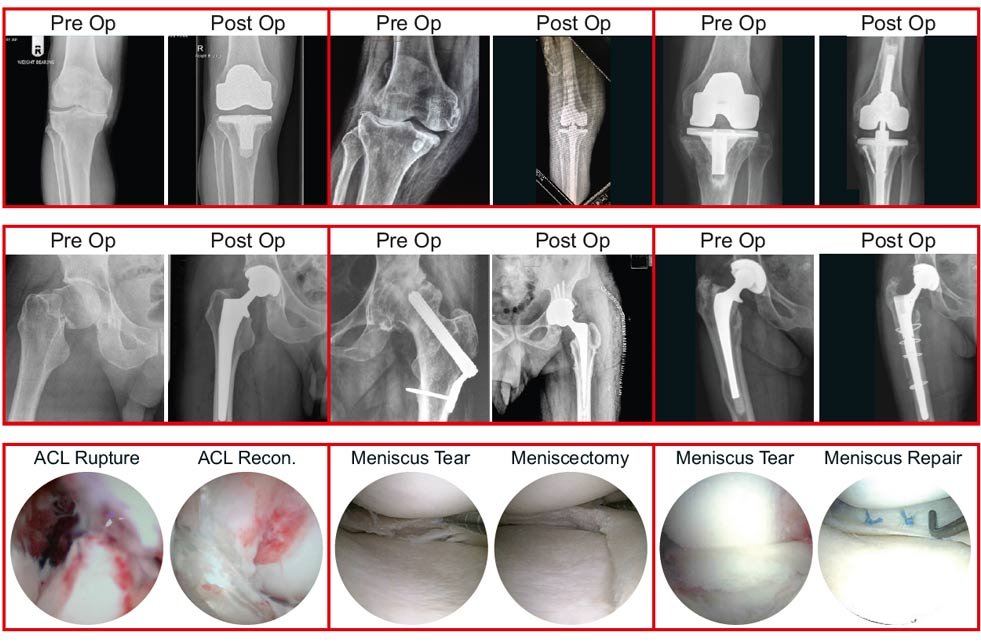

Joint Replacement Surgeries

HIP

KNEE

ANKLE

Sports Injury Surgeries

KNEE ARTHROSCOPY

ANKLE ARTHROSCOPY